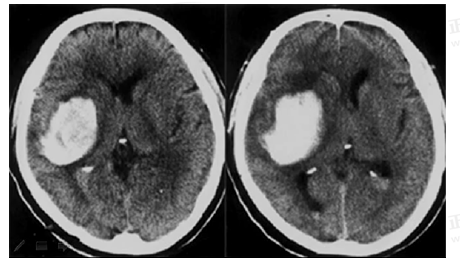

男55歲,左側(cè)肢體偏癱4小時(shí),有高血壓史,診斷為

A.急性硬膜下血腫

B.急性硬膜外血腫

C.顱骨骨折

D.急性腦梗死

E.急性腦出血

【答案】E